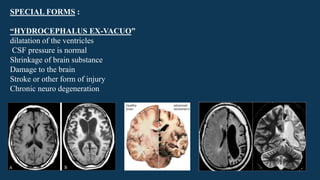

“HYDROCEPHALUS EX-VACUO”

dilatation of the ventricles

CSF pressure is normal

Shrinkage of brain substance

Damage to the brain

Stroke or other form of injury

Chronic neuro degeneration